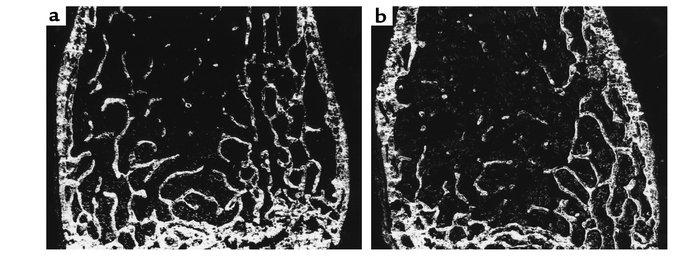

Undecalcified sections of the distal femur of (a) an 8-month-old Fgf2+/+ mouse and (b) a Fgf–/– mouse (dark-field illumination). Trabecular number is decreased in the secondary spongiosa of the Fgf2–/– mouse.